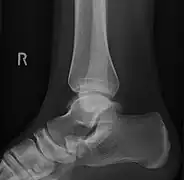

Images radiologiques

De gauche à droite : types 1, 2 et 3

Projection latérale de type 2